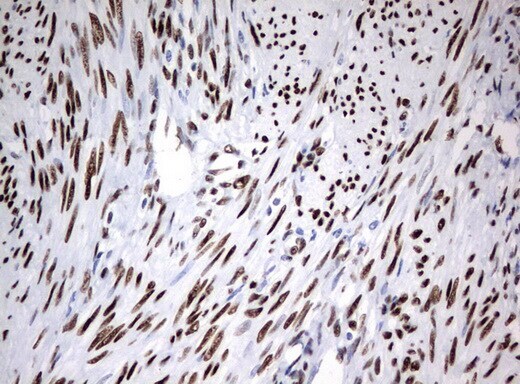

- Submitted by

- Invitrogen Antibodies (provider)

- Main image

- Experimental details

- Immunohistochemical staining of paraffin-embedded Carcinoma of Human liver tissue using anti-ZSCAN18 mouse monoclonal antibody. (UM500081; heat-induced epitope retrieval by 10mM citric buffer, pH6.0, 120°C for 3min)